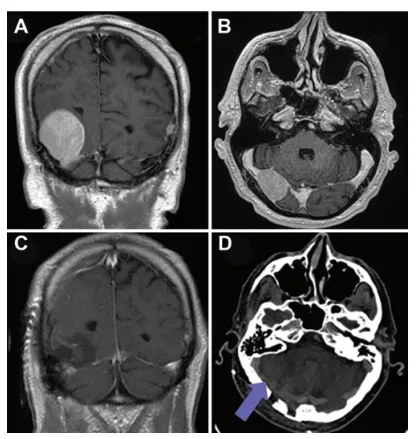

一名69岁男性患者因轻度头部外伤行影像学检查,发现右侧小脑幕存在一个4×3×4厘米的均匀强化硬膜外病变,该病变侵犯右横窦(图1A、B)。

患者接受了右枕部开颅术。术中探查显示肿瘤下极侵犯横窦壁。在完整切除肿瘤及受累窦壁后,采用同种异体组织移植物(AlloDerm, LifeCell Corp.)对静脉窦进行重建。为预防修复后静脉窦血栓形成,术中经直肠给予600mg阿司匹林并静脉注射1000单位肝素。术后住院期间每日维持81mg阿司匹林治疗。病理分析结果符合WHOⅠ级脑膜瘤。

术后第1天磁共振成像显示肿瘤已实现全切除,而CT静脉造影显示修复节段的横窦存在部分闭塞,远端血流已获充分重建(图1C、D)。尽管患者临床状况稳定,仍启动了全剂量抗凝治疗以预防血栓扩展,并于术后第3天出院。

图1. 病例1,术前冠状位(A)与轴位(B)增强T1加权磁共振图像显示右侧小脑幕区一类圆形、均匀强化的轴外病变侵犯横窦。术后冠状位增强T1加权磁共振图像(C)显示肿瘤大体全切除。术后轴位脑CT静脉成像(D)显示右侧横窦部分血栓形成(箭头所示)。